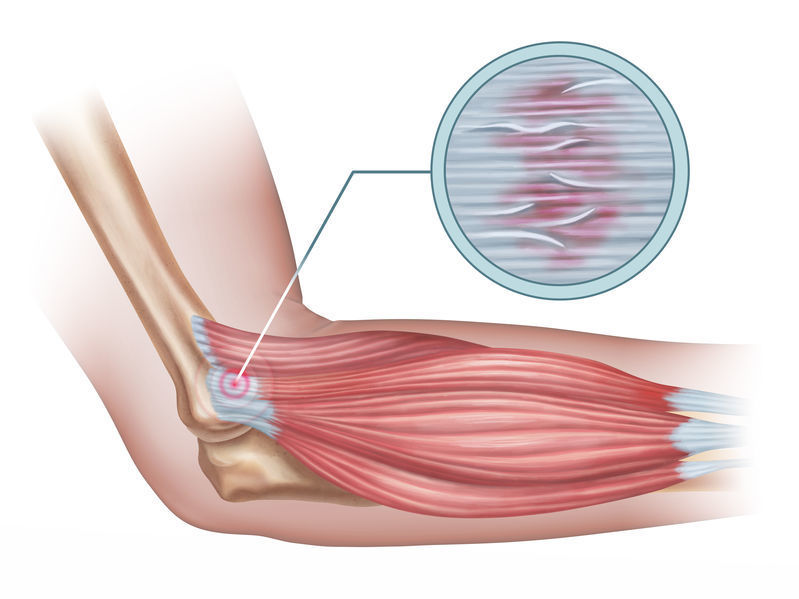

テニスプレーヤーの3~5割の人が経験したことがあるテニス肘とは、

テニス愛好家に多い症状であることから、通称「テニス肘(テニスエルボー)」と呼ばれ、

正式には「上腕骨外側上顆炎(じょうわんこつがいそくじょうかえん)」という肘の病気です。

手首に負担がかかる動作を行った際、肘の外側から伸筋腱に沿って(肘から手首の背側部分)痛みが起こる症状のことを指します。

テニス肘の原因

繰り返す手関節伸筋群のオーバーユース

テニスプレーヤーに発症が多いのは打球する際、ラケットでボールを打つ時の衝撃(インパクト)が手首から手関節伸筋群に強い収縮力が起き、手関節伸筋群の付着部である肘外側に繰り返し加わり続ける事で、付着部に炎症が起き右肘外側に痛みが出ます。

何度も何度も「ラケットを振る」という同じ動作を何度も繰り返し行うことが、付着部に炎症を起こします。特にバックハンドストロークの方が使うので、強い痛みを感じます。

年齢などによる、組織変性など

40代以降で発症する人がぐーんと増えると言われており、年齢も要因のひとつです。

一般的に、人間の身体は、年齢を重ねるにつれて、ゴムのようなしなやかさが失われてきます。腕の筋肉も例外ではありません。

筋肉が硬くなると、同じ負担がかかっていても、微細な損傷が起きやすくなります。手首を使う頻度や、強さは変わっていないのに、年齢が高くなるほど痛みが起きやすいのは、これらも原因の一つです。